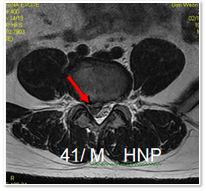

퇴행성 척추관절 질환은 척추의 기능적 단위를 이루고 있는 추간판과 후관절에서 주로 발생하게 됩니다. 추간판은 우리 몸에 전해지는 하중과 외부 충격을 흡수해 주는 완충작용을 하는데, 말랑한 젤리 같은 내부구조를 견고하고 질긴 주머니가 싸고 있는 구조로 되어있습니다. 디스크 탈출증은 이러한 젤리 주머니가 터지는 병적 상태입니다. 나이가 들어가면서 장기간의 노동과 무리한 운동을 통하여 오랜 시간 조금씩조금씩 척추의 구조에 퇴행성 변화가 오게 됩니다. 마치 오래된 소나무가 구부러지는 것처럼 어쩌면 너무나 자연스러운 변화일 수도 있습니다. 문제는 이로 야기된 변형, 운동제한과 통증을 어떻게 덜어 주느냐 하는 것입니다. 흡연, 척추 퇴행성 변화 가속시키는 대표적인 환경적 요인 척추 퇴행성 변화는 역학적 요인, 유전적 요인, 환경적 요인 등 여러 원인이 관여를 하고 있는데, 흡연은 척추 퇴행성 변화를 가속시키는 대표적인 환경적 요인입니다. 퇴행성 척추 질환이 되는 과정은 기능장애 단계, 불안정 단계, 안정화 단계의 세 단계로 되어있습니다. 기능장애 단계에서는 통증은 있으나 병소가 미미하고 적절한 치료를 통해서 완치가 가능한 시기입니다. 이시기에는 아주 특별한 경우를 제외하고는 충분한 휴식과 적절한 약물 및 재활 운동치료로 효과적이고 바람직한 결과를 볼 수 있습니다. 불안정 단계는 척추의 손상된 부위가 회복되지 않은 상태로 반복적으로 다치게 되면서 추간판의 변성과 후관절 등에 병이 심화된 단계입니다. 정확하게 이 단계를 구분하기는 전문가도 어려운 일이지만, 이 단계에서는 치료가 더욱 어려워지고 경우에 따라서 유합술 등의 수술적 치료가 필요하기도 합니다.

안정화 단계에서는 추간판이 거의 역할을 잃어버리고 척추가 뻣뻣하게 굳어버리게 되어 운동제한이 발생합니다. 이 단계에는 척추 자체는 굳어지게 되고 척추내의 신경이 눌려서 발생하는 척추 협착증으로 고생을 하게 됩니다. 이 시기에 치료에는 약물치료, 주사요법, 수술적 치료로 나누어 볼 수 있습니다. 척추관 협착증의 초기에는 여러 다양한 약물들이 치료에 이용되고 있습니다. 신경인성 염증치료와 혈류 개선제, 소염진통제, 항우울제, 근이완제 등을 증상에 따라 적절히 사용하여 그 증세의 호전을 기대 할 수 있습니다. 그리고 약물치료와 물리치료와 같은 보존적 치료가 효과적이지 못한 경우 경막외 스테로이드 주사요법을 고려해 볼 수 있습니다. 그리고 방사선 검사 및 MRI 검사에서 매우 심하게 척추관이 좁아져 있거나, 보존적 치료에도 효과가 없고, 보행거리가 점점 짧아지고 서있기가 어려워 질 때, 심한 통증과 배뇨 배변장애가 있을 때는 수술적 치료가 필요합니다. 척추 퇴행성 질환은 나이가 들어가는 정상적인 생물학적 과정과 구분하기가 어렵습니다. |